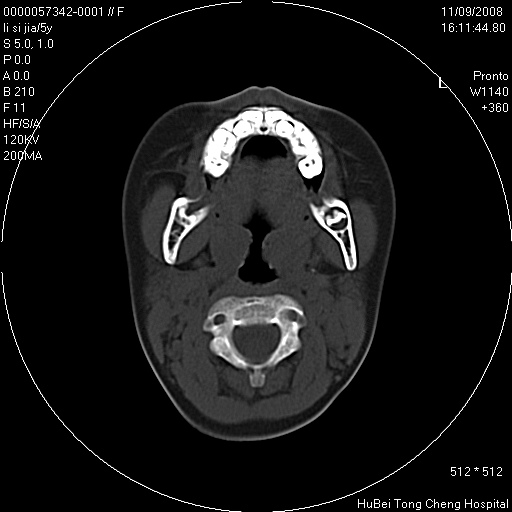

患儿 女,5岁。鼻塞、流涕2年余。

临床诊断:慢性副鼻窦炎?

副鼻窦ct轴位平扫(层厚、层距均为5mm),图像如下:

双侧上颌窦\\筛窦及蝶窦内均可见多量软组织密度影,结合病史支持考虑慢性全鼻窦炎

双侧上颌窦、筛窦及蝶窦内均可见粘膜增厚,结合病史支持考虑慢性全付鼻窦炎,腺样体肥大。